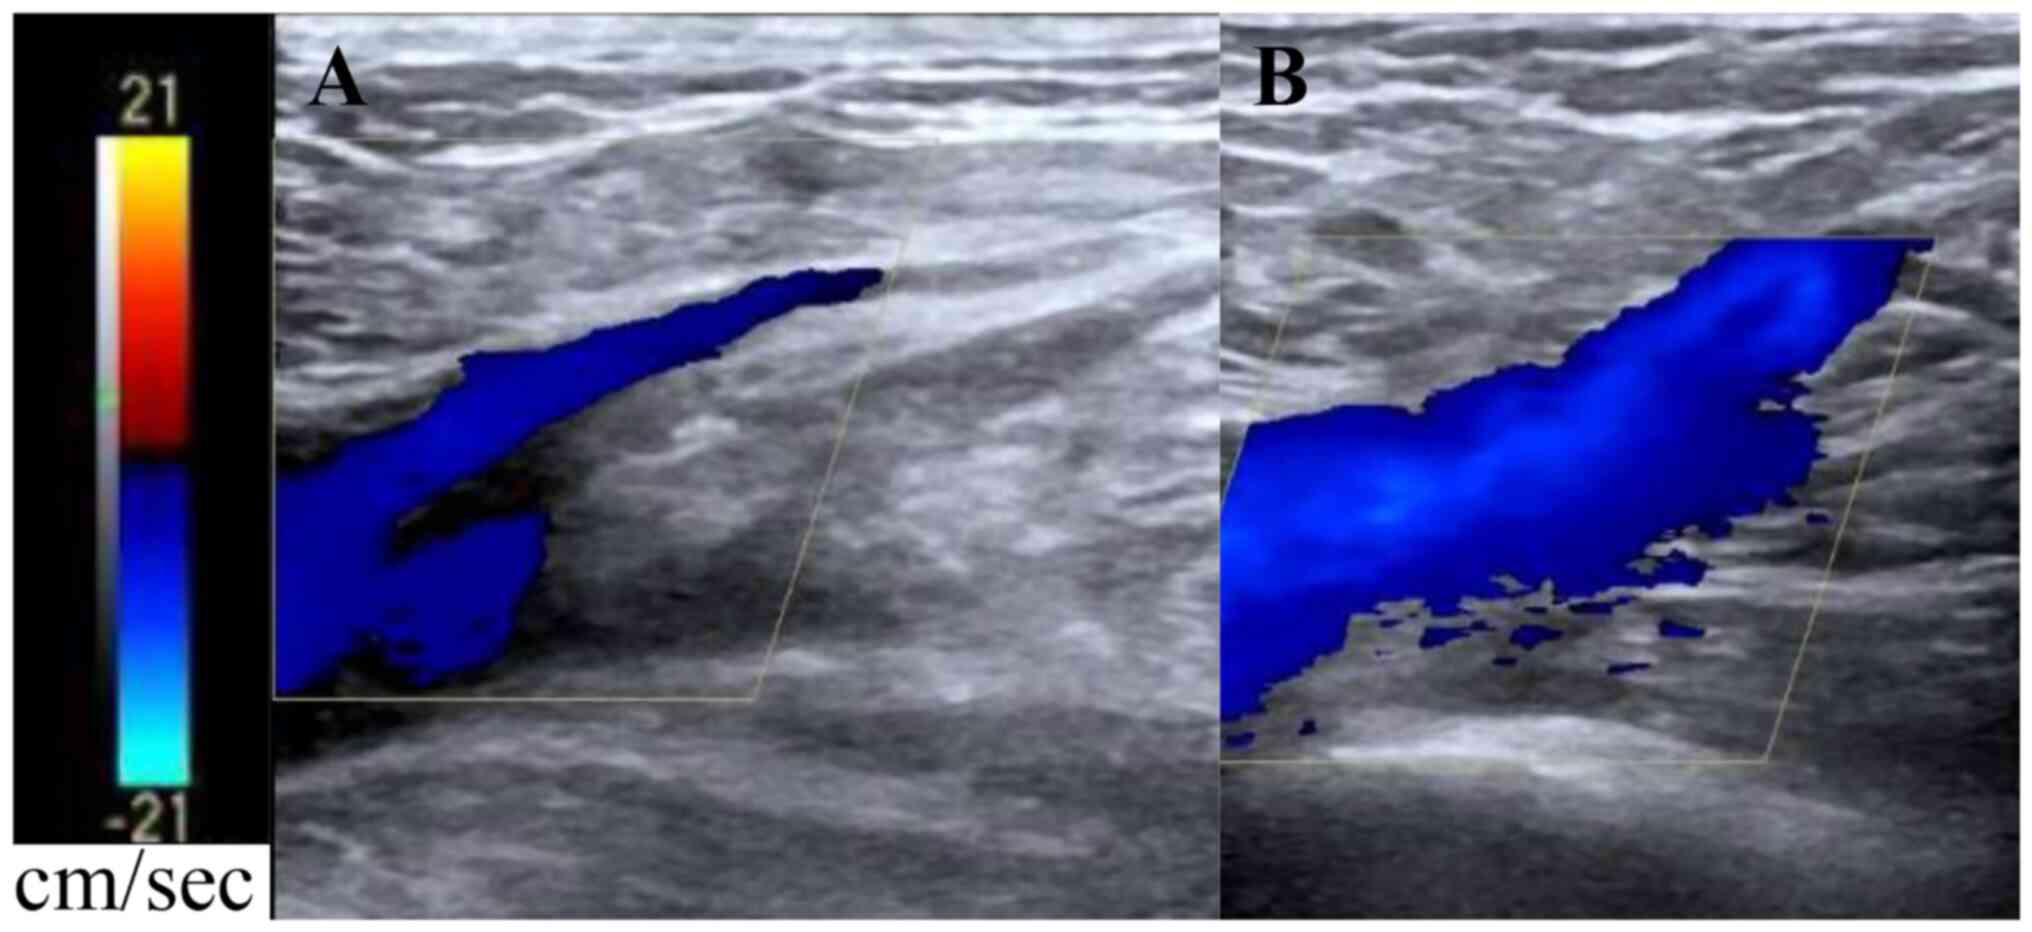

No apparent venous thrombosis was found by lower extremity venous ultrasonography 10 days after the surgery (Fig. 6A and B). To clear the SAH in the patient, lumbar spinal catheter drainage was performed on the first day after the operation. On the fourth day after the operation, the catheter was removed and a lumbar puncture was performed once a day for seven consecutive days to release the cerebrospinal fluid (CSF). The CSF became transparent and clear, while the patient was conscious and responsive. The muscle strength of both lower extremities returned to grade II two weeks after the operation. The patient was discharged three weeks after the operation and transferred to a rehabilitation hospital for further treatment. The patient was treated with cognitive and physical exercise in the rehabilitation hospital. The muscle strength of the patient's lower extremities was grade III one month after the operation and returned to grade V 60 days after the operation. The patient revisited the hospital for re-examination six months after the operation and his nerve function was found to be normal. A two-year follow-up cranial DSA indicated satisfactory embolization of the aneurysm (Fig. 7).

Figure 6

Color Doppler ultrasound of lower limb veins of the patient 10 day after the surgery. (A) Image of the inflow segment of the great saphenous vein into the femoral vein when the patient held his breath. (B) Image of the inflow segment of the great saphenous vein into the femoral vein when the patient was breathing normally. The blood flow in the vascular lumen of lower limbs of the patient was unobstructed and there was no obvious embolism.